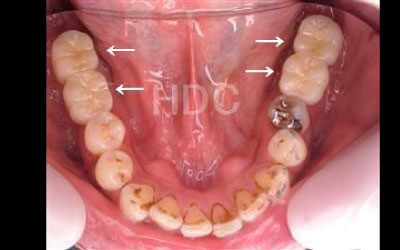

歯が抜けてそのままにしていたら、周囲の歯が動いてしまいました。どうすればいいでしょうか?

小さなズレであれば調整や詰め物で対応可能ですが、歯が大きく傾いている場合は矯正治療や被せ物が必要になることがあります。ズレが進行する前に、早めに歯科医院での診査・治療を受けることをおすすめします。

2 歯が傾いてくる、落ちてくる

歯はお互いに支え合ってバランスを保っています。つまり、歯が抜けるとその支えがなくなり、抜けた部分の隣の歯が傾いたり、上の歯が下にずれてくることがあります。